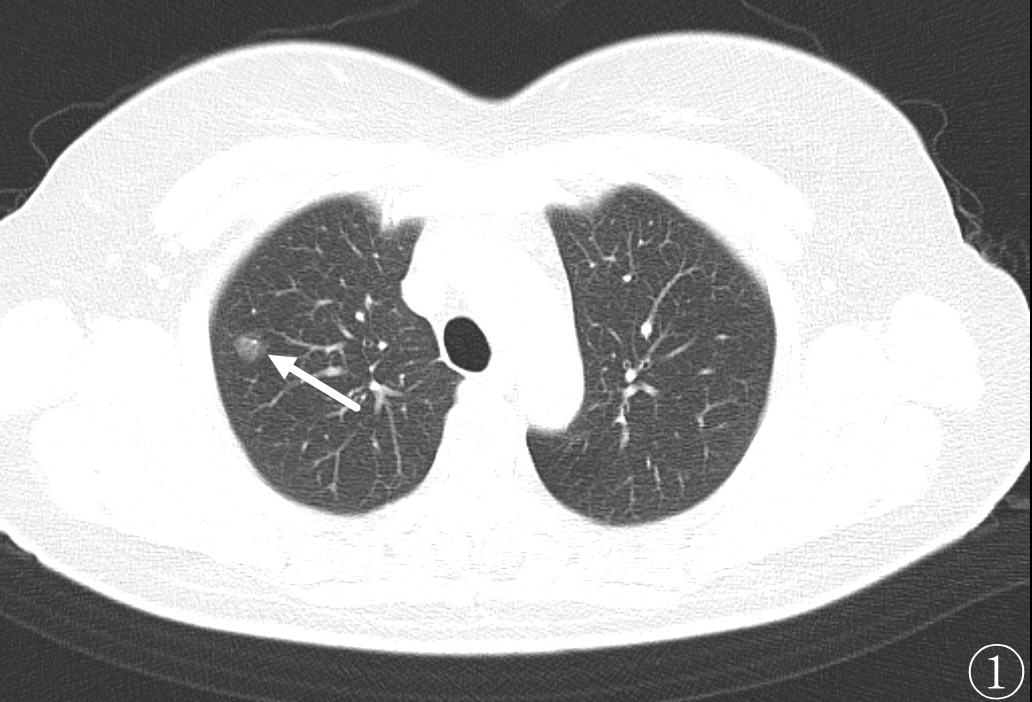

术前进行常规CT扫描确定消融区域及穿刺路径,局部麻醉后利用微波消融针,从体表定位点沿着穿刺路径逐层穿刺到达预定消融区域(图②),予以单次多点消融靶区,最后可见消融后靶区完全覆盖病变区域(图③、④)。手术过程仅耗时约1h,术中肺尖可见少量出血,未发现气胸及咯血等并发症,术后3天复查影像可见消融区完全覆盖病灶(图⑤),病人安然出院,从而达到治愈性消融的目的。